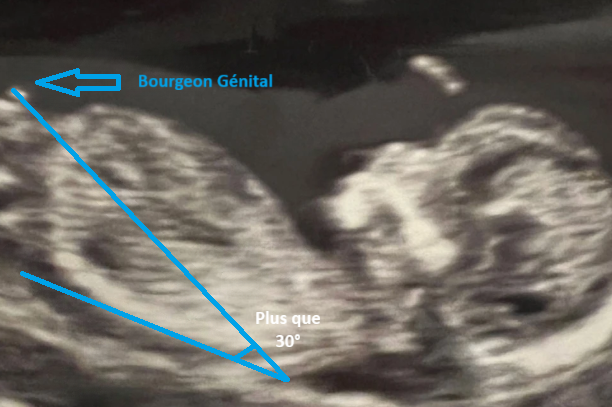

Pour un futur garçon 💙

Le bourgeon s'oriente vers le haut, formant un angle significativement supérieur à 30° par rapport à la ligne de la colonne. Il est plus proéminent et semble « pointer » vers le ciel.